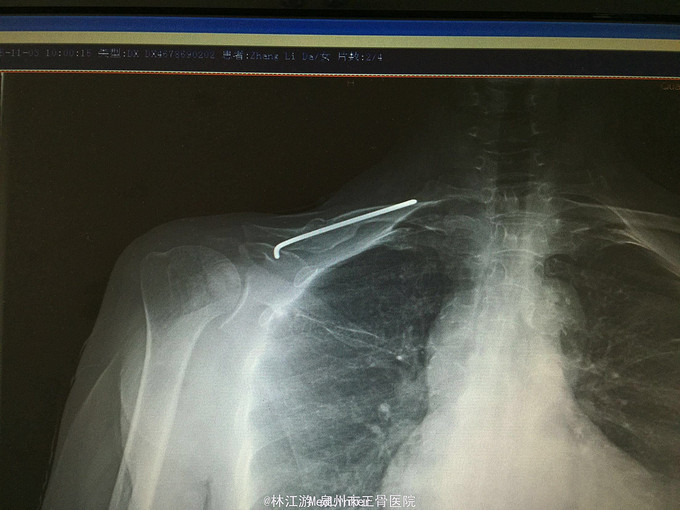

右锁骨粉碎性骨折闭合复位克氏针内固定术

摔伤致右肩部肿痛活动受限3小时

右锁骨部肿胀,锁骨中段压痛明显,可及明显骨擦感,右肩活动受限,肢端感觉活动正常

右锁骨粉碎性骨折 行闭合复位克氏针内固定术